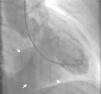

Transthoracic echocardiography revealed a thrombus partially filling a giant pseudoaneurysm/aneurysm of the inferoposterior wall, causing significant deformation of the ventricular geometry (Figure 1; Videos 1–4). Despite the size of the aneurysm, the subvalvular mitral apparatus was intact, with no regurgitation. Given the uncertainty surrounding the differential diagnosis, cardiac magnetic resonance imaging was performed, which confirmed a giant ventricular aneurysm (long axis 6.7 cm) containing a thrombus (Figure 2; Videos 5 and 6), and anticoagulant therapy was begun. Myocardial perfusion scintigraphy excluded ischemia and confirmed necrosis of the inferoposterior territory. Preoperative cardiac catheterization showed chronic occlusion of the proximal right coronary artery but no significant left coronary disease, while ventriculography documented a large ventricular aneurysm (Figure 3; Video 7). The patient underwent surgical repair of the aneurysm of the left ventricular inferior wall (Figure 4) by partial aneurysmectomy under extracorporeal circulation, with removal of a large wall thrombus and closure of the aneurysm neck with a 2 cm × 3 cm Dacron® patch (Figure 4). The left ventricle was closed using continuous sutures. The postoperative period was uneventful and the patient was discharged home on the fifth postoperative day.

Cardiac cine steady-state free precession magnetic resonance imaging: (A) long-axis view showing a giant ventricular aneurysm (long axis 6.7 cm) of the posterior wall (arrow) containing a thrombus; (B) short-axis view above the level of the papillary muscles showing a large ventricular aneurysm of the inferoposterior wall (arrow), containing a thrombus.